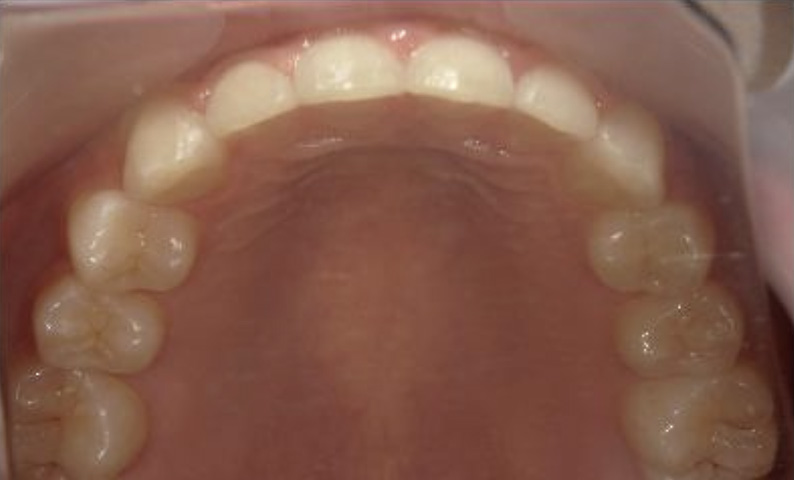

症例_001 下顎だけの部分矯正

治療期間:6ヶ月金額:27万円+税女性前歯のガタガタ下の前歯だけ

| Before | After |

|---|---|

|